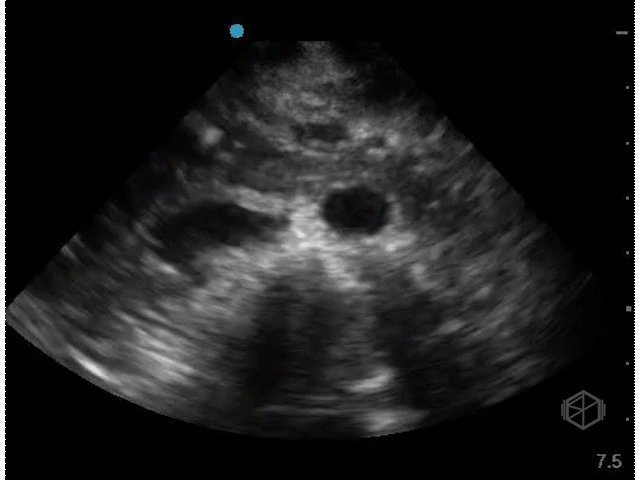

The next SonoProp goes to Dr. Obioma Nkemakolam.

He was evaluating a 54-year-old male with a history of hypertension, hyperlipidemia, coronary artery disease, and current everyday smoking, who presented with shortness of breath. The patient was significantly hyperglycemic and was thought to be in DKA. He was also borderline hypotensive and there was a lacy appearance to his abdomen. The patient had a stat abdominal aorta scan that demonstrated the following:

There is a large circular anechoic structure in the middle of the scan. If you thought this was the abdominal aortic aneurysm — surprise — it’s not.

This a distended fluid filled stomach, a common false positive for FAST/FAFF examinations as well as aorta exams.

Patient had a CTA that demonstrated a normal aorta as well as diffuse gaseous distention of the esophagus mild/moderate gastric distention with fluid and gas due to recent alimentation.

Diagnosis: Distended stomach filled with liquid/food

• The aorta has some key landmarks that should be identified before determining the structure is the aorta on ultrasound - the vertebral body should be right behind it. The IVC should be next to it on the left. The spinal body should be visualized. The aorta is also pulsatile and will have the celiac trunk (if the proximal aorta can be visualized) and superior mesenteric artery visible.

• This structure seems to be coming from the left upper quadrant, with no vertebral body behind it and no IVC next to it. The color doppler signal is unreliable due to the patient’s heavy breathing.

• The stomach will appear as a cystic organ when distended with fluid. If there is clear fluid there may be echogenic gas bubbles visible (28191199). There many hints that the object in Dr. Nkemakolam’s case is the stomach and not the aorta.

• Breathing and peristalsis of the stomach may cause doppler noise.